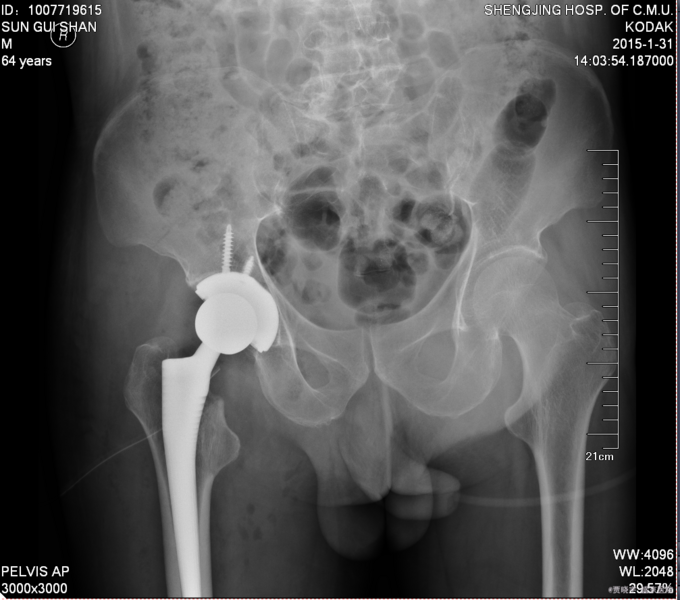

患者入院后给予皮牵引治疗后,完善相关检查,查无明显手术禁忌症后,CSEA下行左人工全髋关节置换术,术后给予抗炎,消肿,等对症治疗。患者每天换药观察切口愈合情况,无红肿及渗出,待伤口14天后予以拆线治疗,予以出院,给予康复处方。